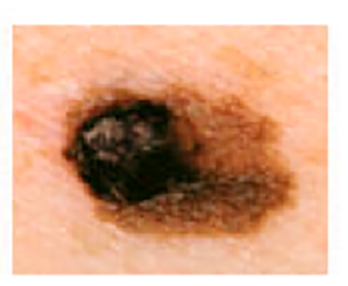

Melanoma Photos

Amelanotic melanomas may be pinkish-looking, reddish, purple, normal skin color or essentially clear and colorless.

The power of denial can be strong. This man believed the large, dark growth on his back was a boil, despite oozing and bleeding for months. He kept bandaging it and thought it was just slow to heal. When he was finally referred to Dr. Sarnoff, a biopsy and other tests revealed a melanoma so large and deep that it had already spread to the man’s liver and brain. He was referred to an oncologist and began an immunotherapy regimen that did not appear to be working, which happens with some patients. (Thanks to recent innovations, there may be other treatment options, including participation in a clinical trial.) This is a powerful reminder of the importance of early detection.